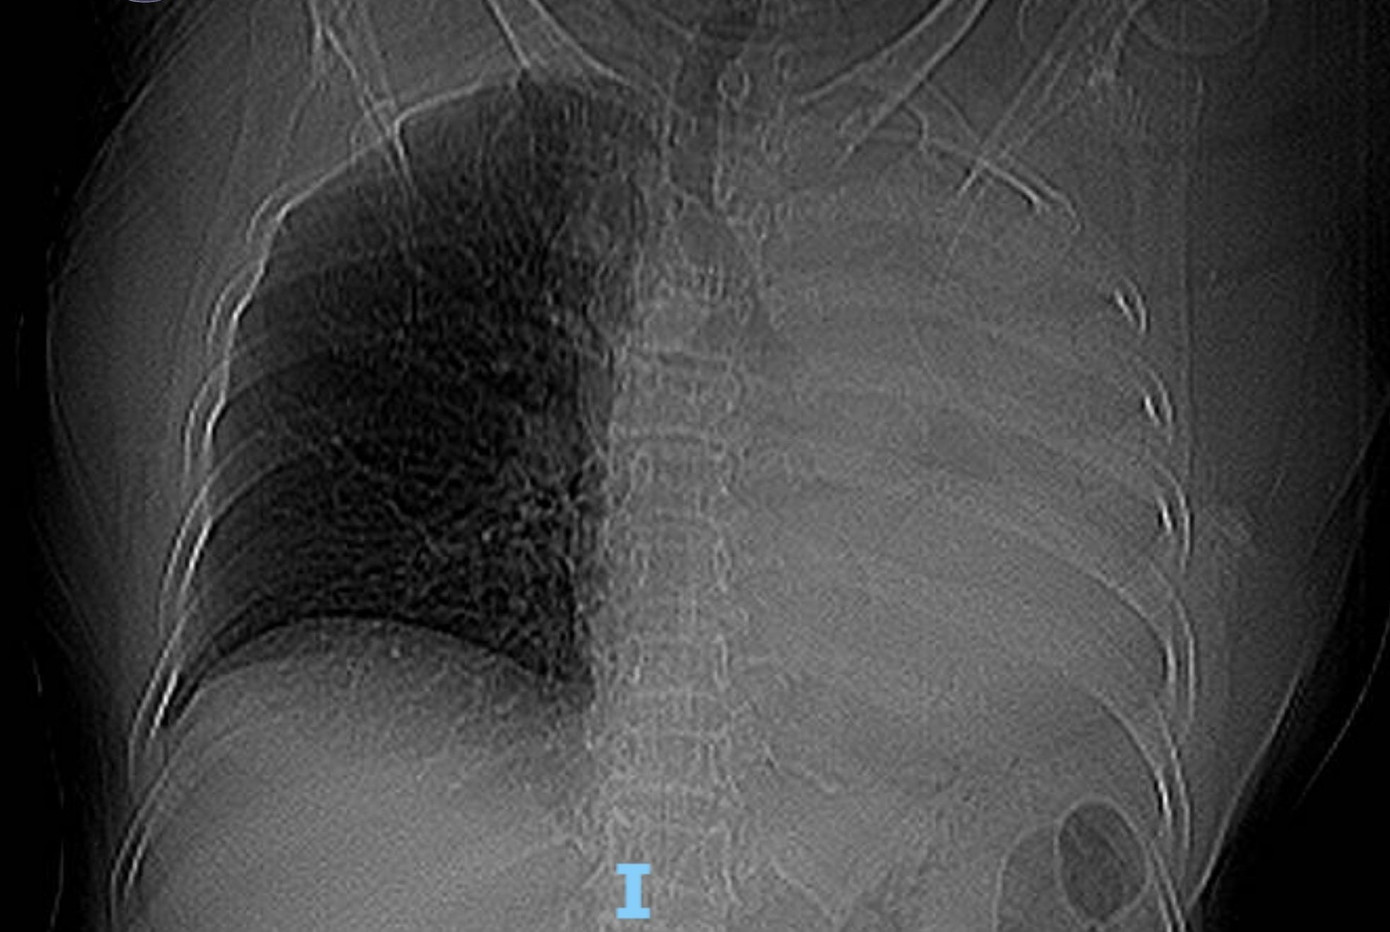

Bệnh nhân là bà T.B. (78 tuổi, trú Đà Nẵng ). Sau khi chụp X-quang ngực, các bác sĩ phát hiện hình ảnh mờ đậm đều toàn bộ trường phổi trái. Kết quả CT cho thấy cụ bà bị xẹp toàn bộ phổi trái do khối tổn thương nằm trong lòng phế quản gốc trái, nghi ngờ u phế quản hoặc dị vật đường thở.

Phim X-quang ngực cho thấy mờ toàn bộ phổi trái.

Với diễn tiến ho và khó thở đột ngột trong vài ngày gần đây, các bác sĩ nhận định khả năng có dị vật đường thở.